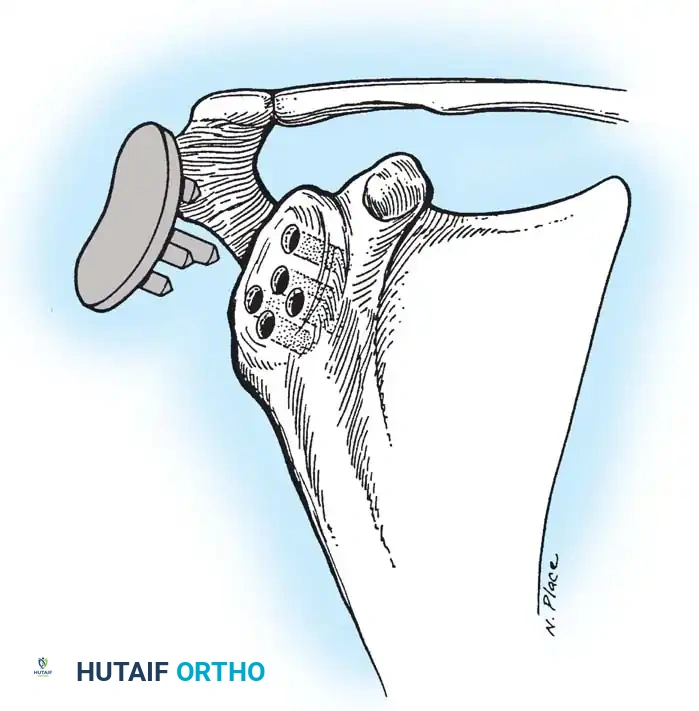

Reverse Total Shoulder Arthroplasty (rTSA)

The rTSA fundamentally alters shoulder biomechanics. By medializing and distalizing the center of rotation, it increases the deltoid moment arm and recruits more anterior and posterior deltoid fibers for elevation, bypassing the need for a functional rotator cuff.

Surgical Nuances for rTSA:

* Glenoid Baseplate: Must be positioned inferiorly on the glenoid to avoid scapular notching. A slight inferior tilt (10 degrees) is often utilized.

* Glenosphere: Typically 36 mm or 42 mm. Larger spheres increase stability and range of motion but may increase the risk of notching.

* Humeral Stem: Often placed in 0 to 20 degrees of retroversion.